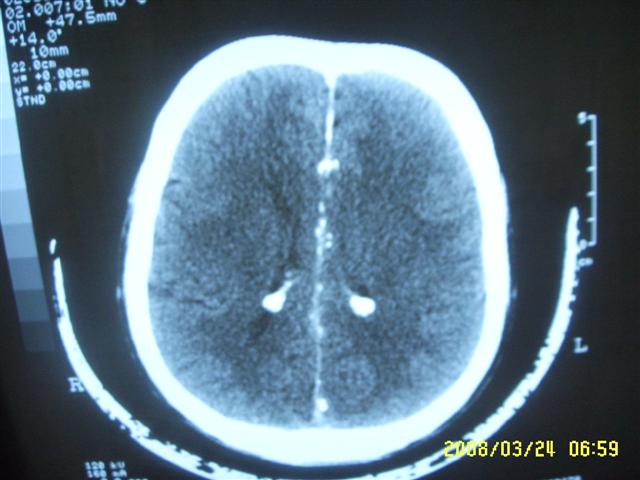

以下是引用dyqct在2008-4-2 20:09:00的发言:[br]考虑为:神经纤维瘤病(nf1型)。建议增强进一步检查。